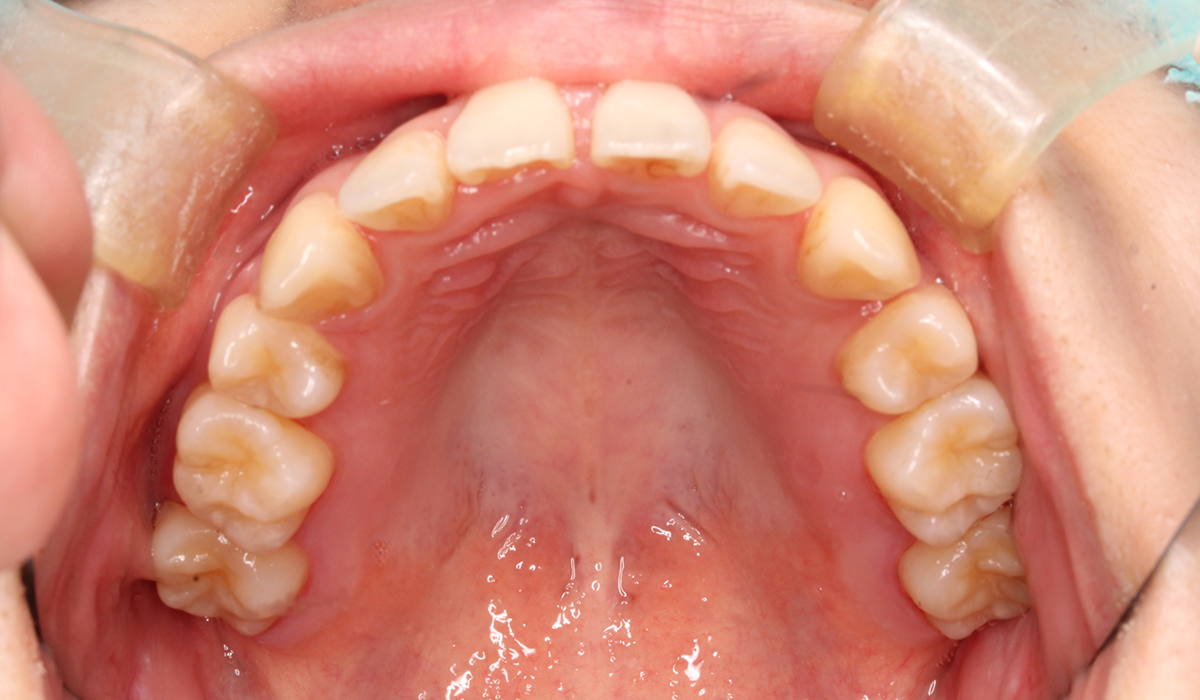

上顎

BK終了時

術後